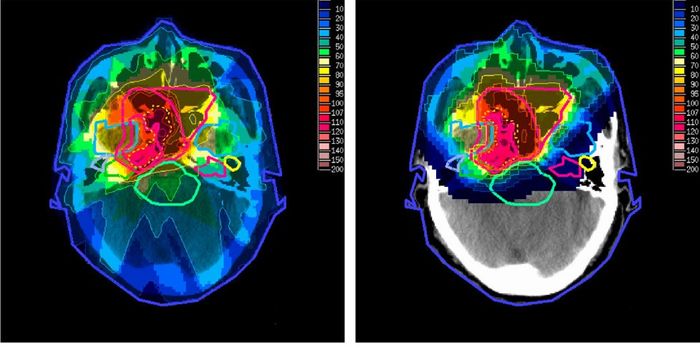

OCT 10, 2016Clinical & Molecular DXA new technique under Phase 1 clinical trial gave surgeons the ability to see a brain tumor glow like they’ve neve ...